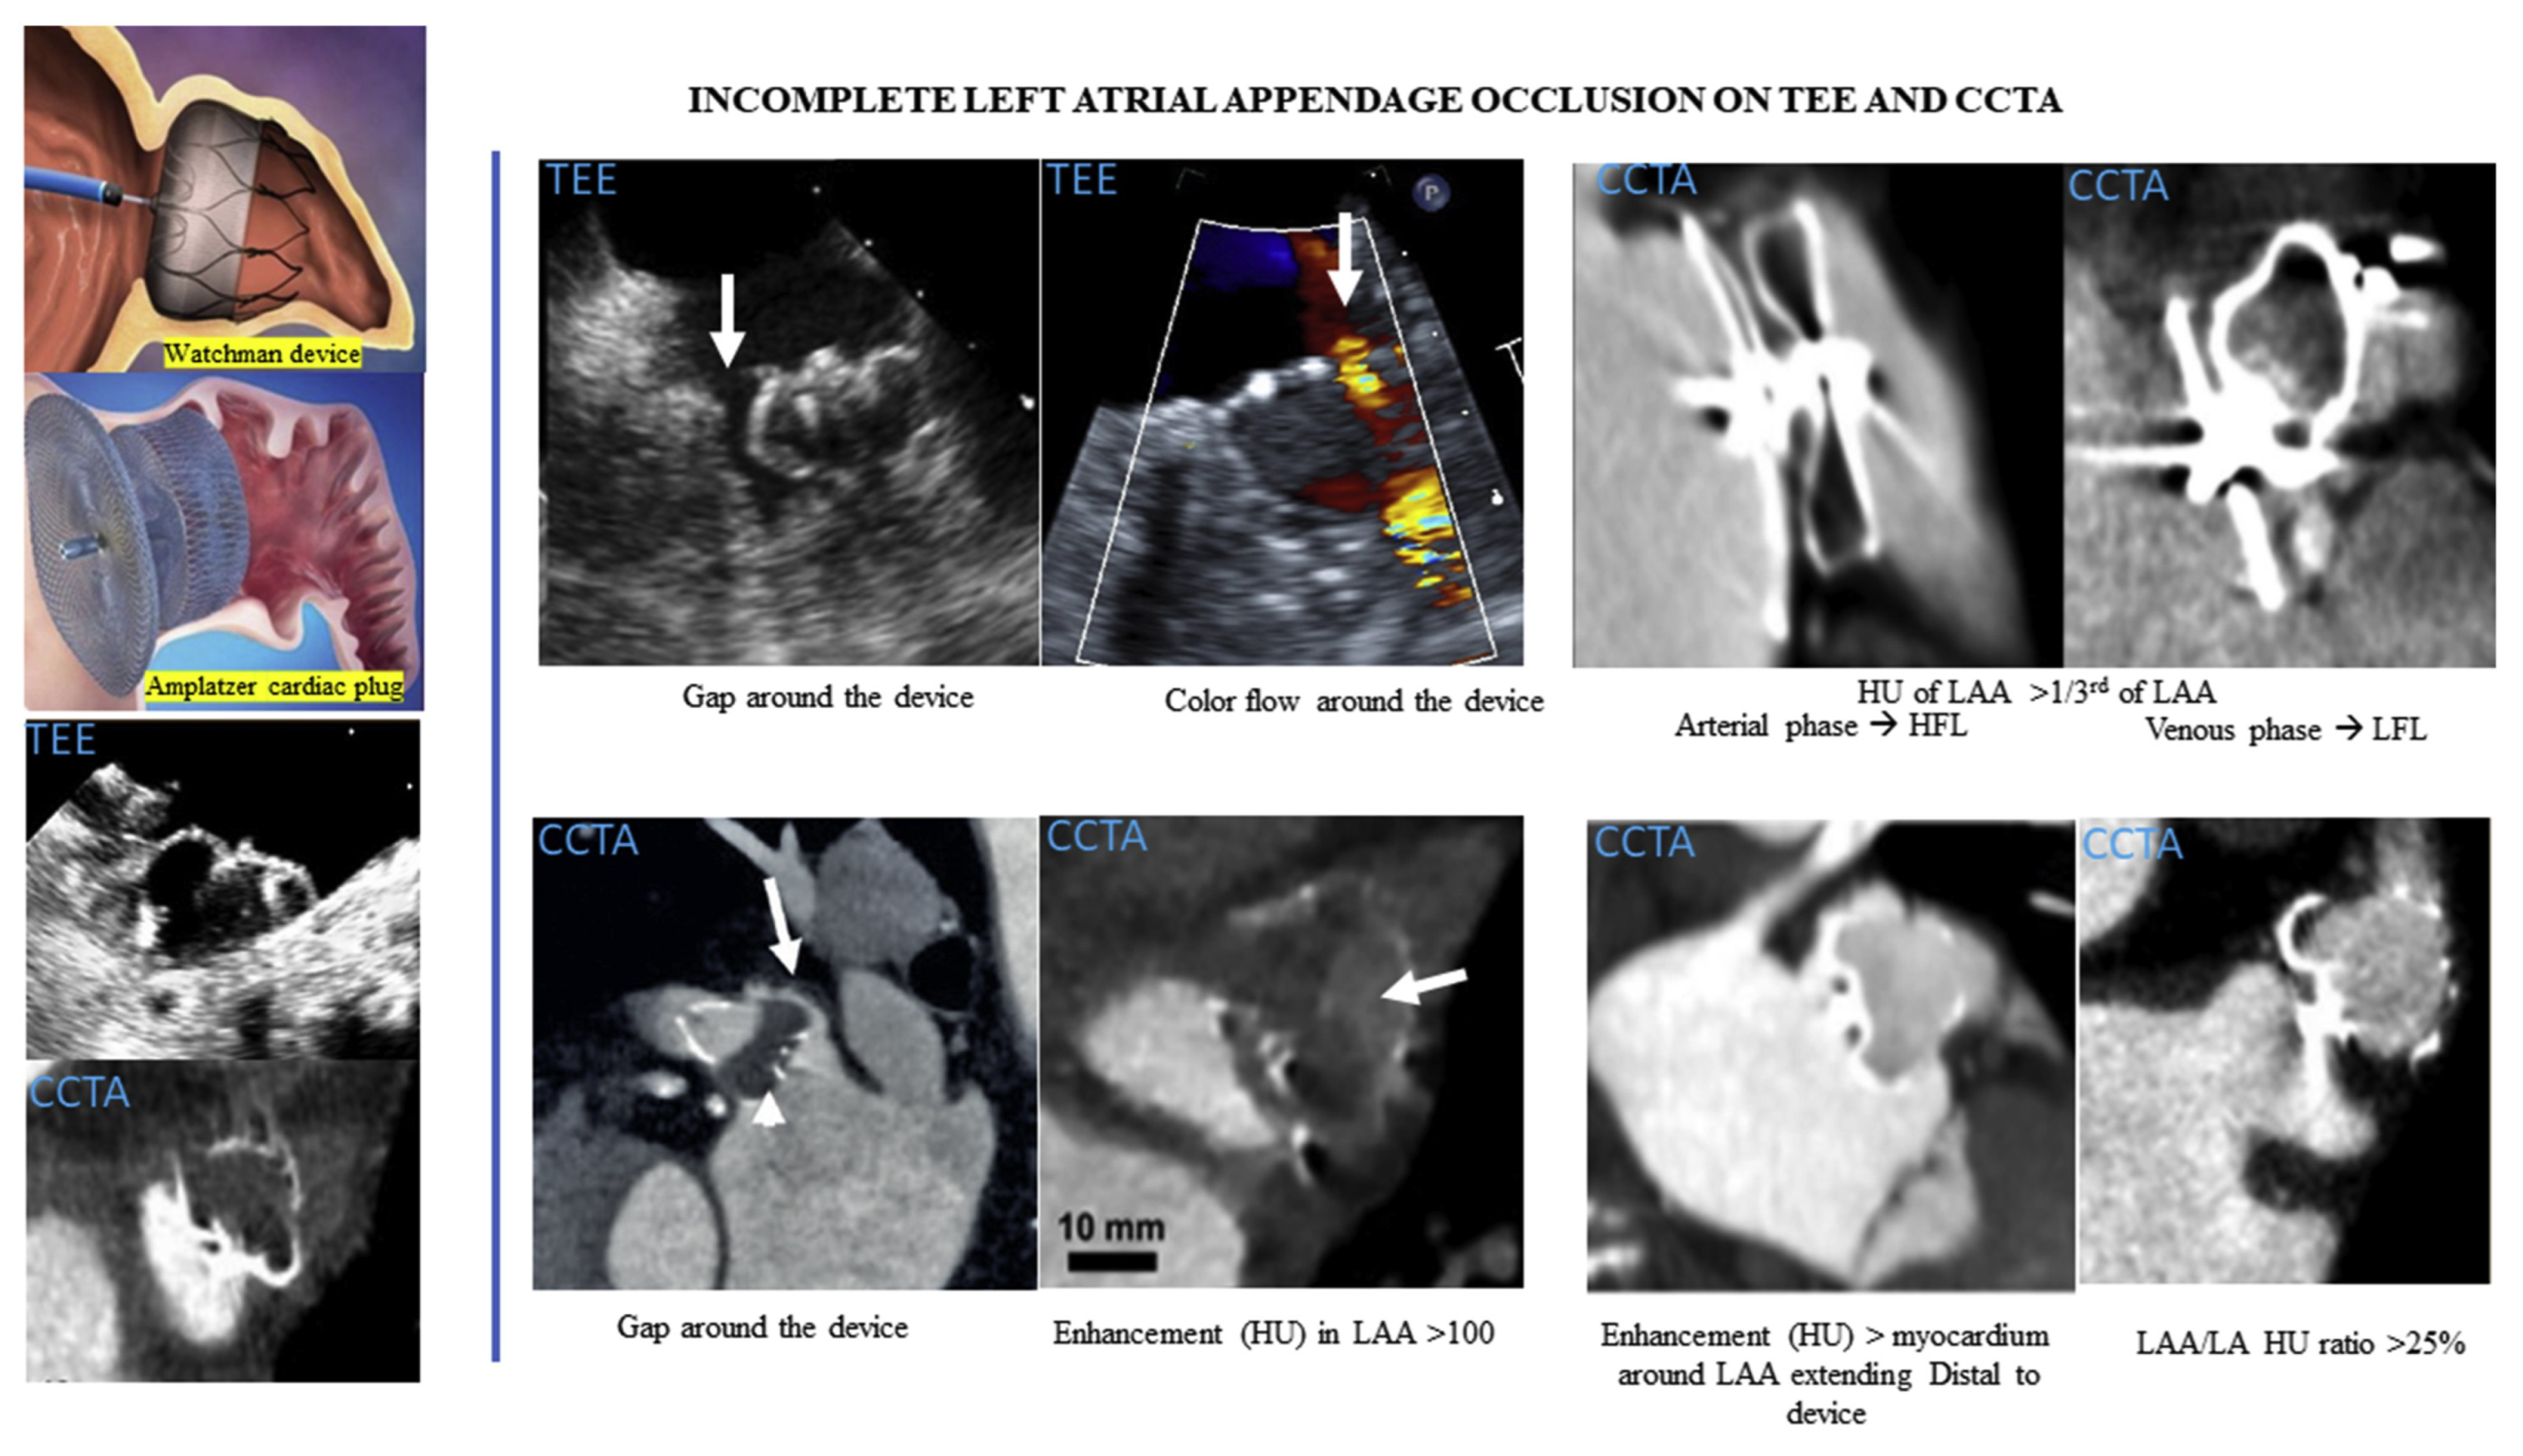

1.3. Imaging Modalities for PDL Detection

1.4. PDL Incidence in Patients Experiencing AF